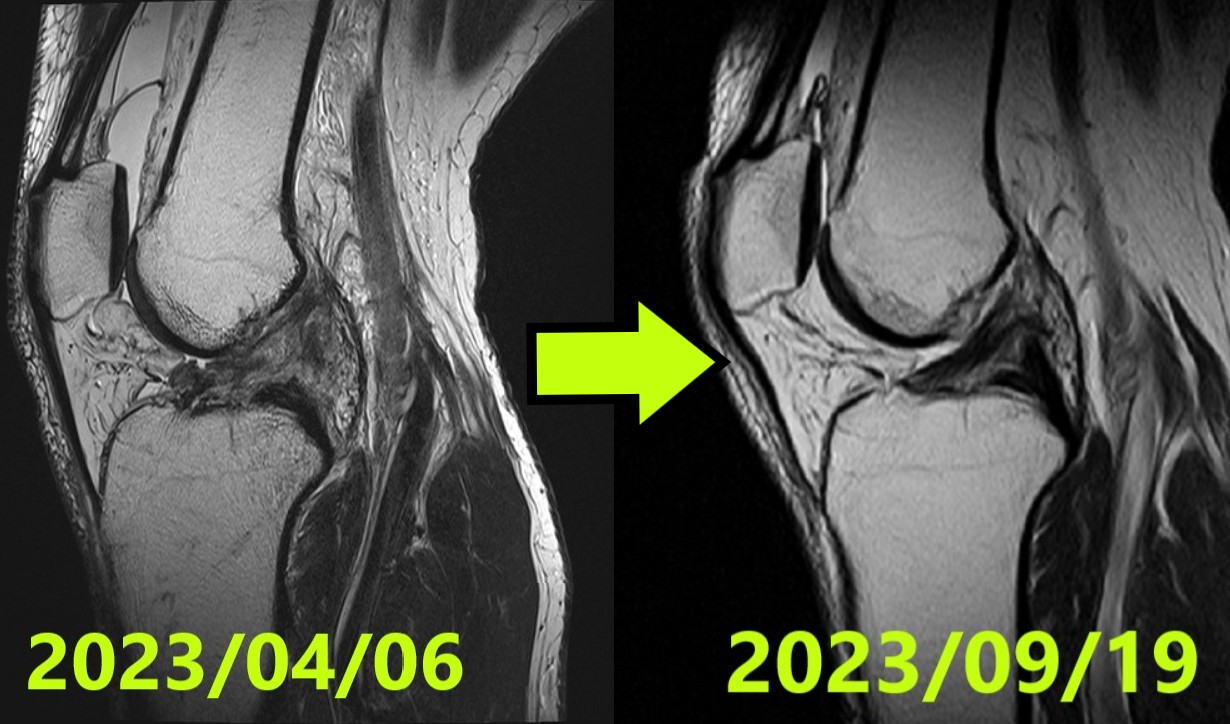

症例50|前十字靭帯断裂の自然治癒(41歳・日本人男性):スノーボード着地での完全断裂から最高評価の再生へ

スノーボードのジャンプ着地で左膝を受傷。3名の専門医による合議制ルールのもと、初診MRI診断では最も重度なIh…